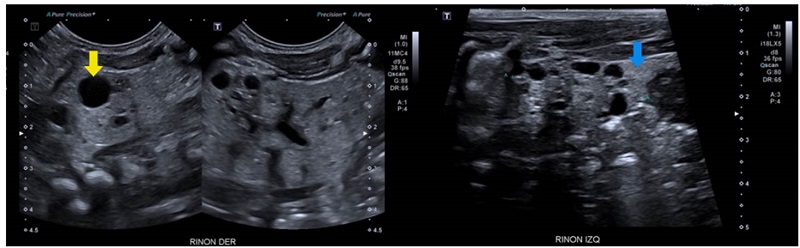

Se trató de un paciente de sexo masculino que a los dos años de vida presentó un cuadro clínico de lesión renal aguda KDIGO 3 en el contexto de una infección gastrointestinal 9. Se practicó una ecografía renal que evidenció la dilatación de las vías urinarias del lado derecho, por obstrucción secundaria a estenosis de la unión pieloureteral, con un riñón izquierdo de apariencia displásica multiquística (figura 1).

Análisis. Los riñones displásicos multiquísticos son masas renales no funcionales, causados por alteraciones en la diferenciación metanéfrica y caracterizados por la presencia de múltiples quistes que reemplazan en su totalidad el parénquima renal. Usualmente, se visualizan en la evaluación ecográfica prenatal; hay afectación de un solo riñón y tienden a involucionar en el útero o después del nacimiento en el 95 % de los casos. Esta condición suele ocurrir de manera esporádica; sin embargo, se han visto casos donde hay agregación familiar o puede presentarse en el contexto de condiciones multisistémicas por mutaciones en los genes EYA1, SIX1, HNF1B y PAX2, entre otros 10.